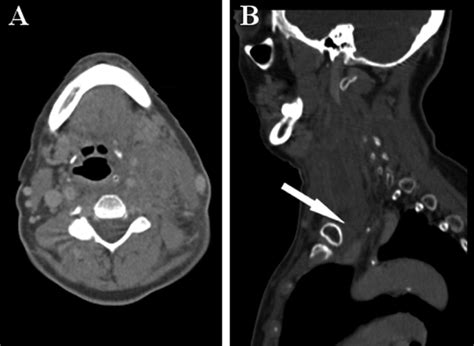

• Arterial Puncture: Puncturing the carotid artery can lead to hematoma formation or arterial injury.